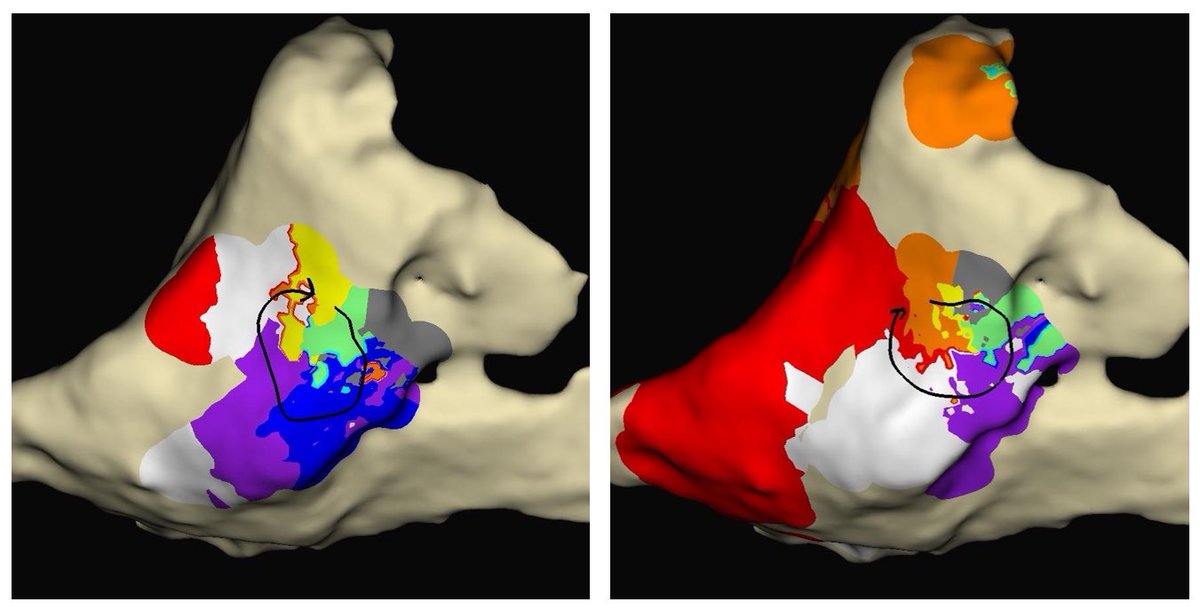

31 yo man. Antidromic ART mimicking OFT VT. Anyone seen/heard of accessory pathway to R-L SOV before? Slowly conducting and pathway potential 82 ms pre-QRS. One burn! Fun case/maneuvers. #EPPeeps @ReddyEPS @DrRigoRamirezEP @DrGregMichaud @jaymontgomery44 @DrRoderickTung @ @KUCVM

11

24

67